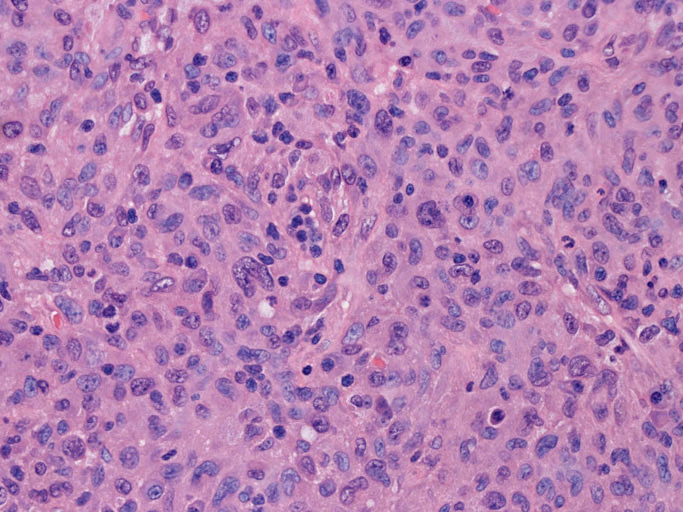

LCSの病理組織所見

Langerhans cell histiocytosisの高悪性度 variantで明らかな悪性像を示すLangerhans cellの腫瘍性増殖と定義される(WHO, 2008)

大型細胞の増殖よりなる腫瘍。縦溝,しわ,切れ込みのある核をもった大型細胞も出現する。クロマチンは顆粒状で核小体も明瞭である。核分裂は >50/10hpfと多い。eosinophilsは少ない。壊死が多発することがある。未分化ないし低分化な細胞像, 組織所見のため鑑別診断は多岐にわたり、的確な免疫染色を行う必要がある。